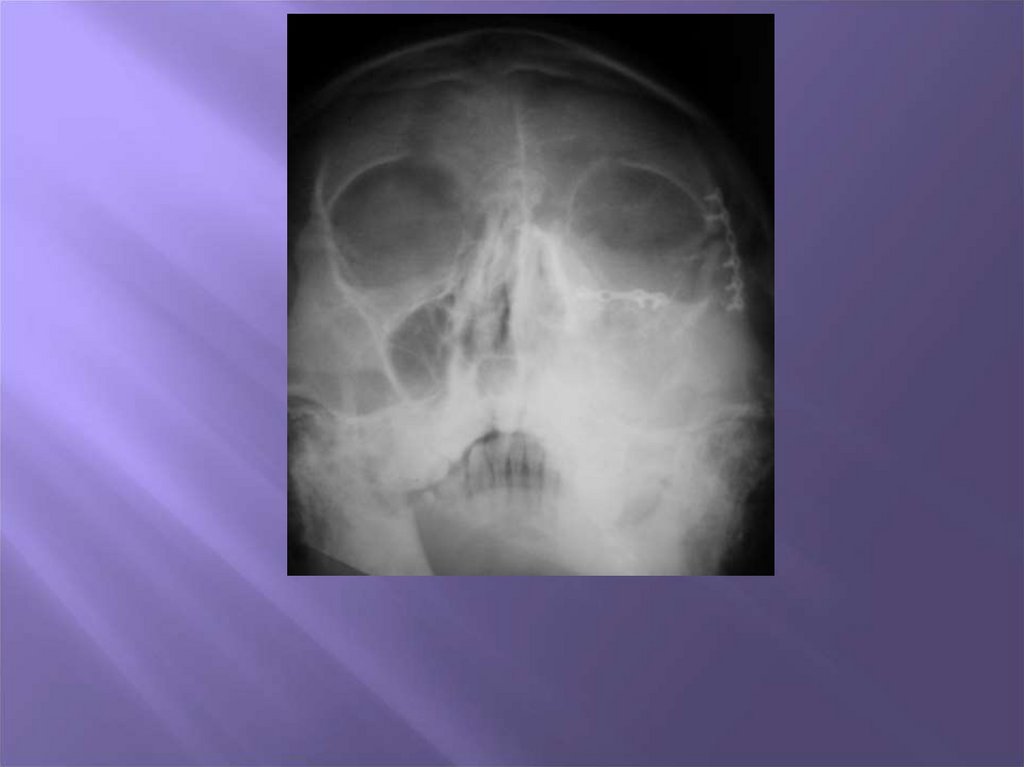

4. Методы обследования пациентов с врожденными и приобретенными дефектами и деформациями скуловой кости , дуги и носа

1. Клинический

2. Рентгенологический

3. Компьютерная томография